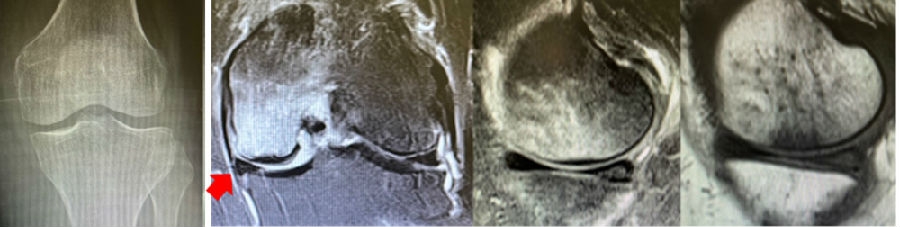

病例1:女,65岁,主诉右膝关节内侧疼痛1周。2018年1月X光未见右膝骨质异常,MR检查见股骨内侧髁骨坏死,半月板相对突出百分比(RPE)28.99%,关节线会聚角1.4°。

予切开行克氏针钻孔减压,口服消炎止痛药物、钙剂及骨化三醇,不负重6周,后改部分负重至3个月。2018年4月复查MR见骨髓水肿基本完全吸收,坏死区局限并修复良好,半月板相对突出百分比(RPE)32.08%,患者临床症状消失。

病例2:女,69岁,主诉左膝关节内侧疼痛1月余。2017年11月X光见右膝股骨髁负重区的软骨下区域出现了椭圆形透亮影,MR检查见股骨内侧髁骨坏死,合并内侧半月板外突和后角层裂,半月板相对突出百分比(RPE)25.32%,矢状位病变区域前后径为23.96mm,关节线会聚角6°。

予克氏针钻减压,消炎止痛药物口服、静滴唑来膦酸钠注射液,避免负重6周,后改部分负重至3个月,患者依从性差。2018年1月复查MR见骨髓水肿少许吸收,坏死区扩大,半月板相对突出百分比(RPE)33.53%,矢状位病变区域前后径为26.89mm,患者仍有膝关节疼痛症状,建议行手术治疗,患者拒绝手术后失访。